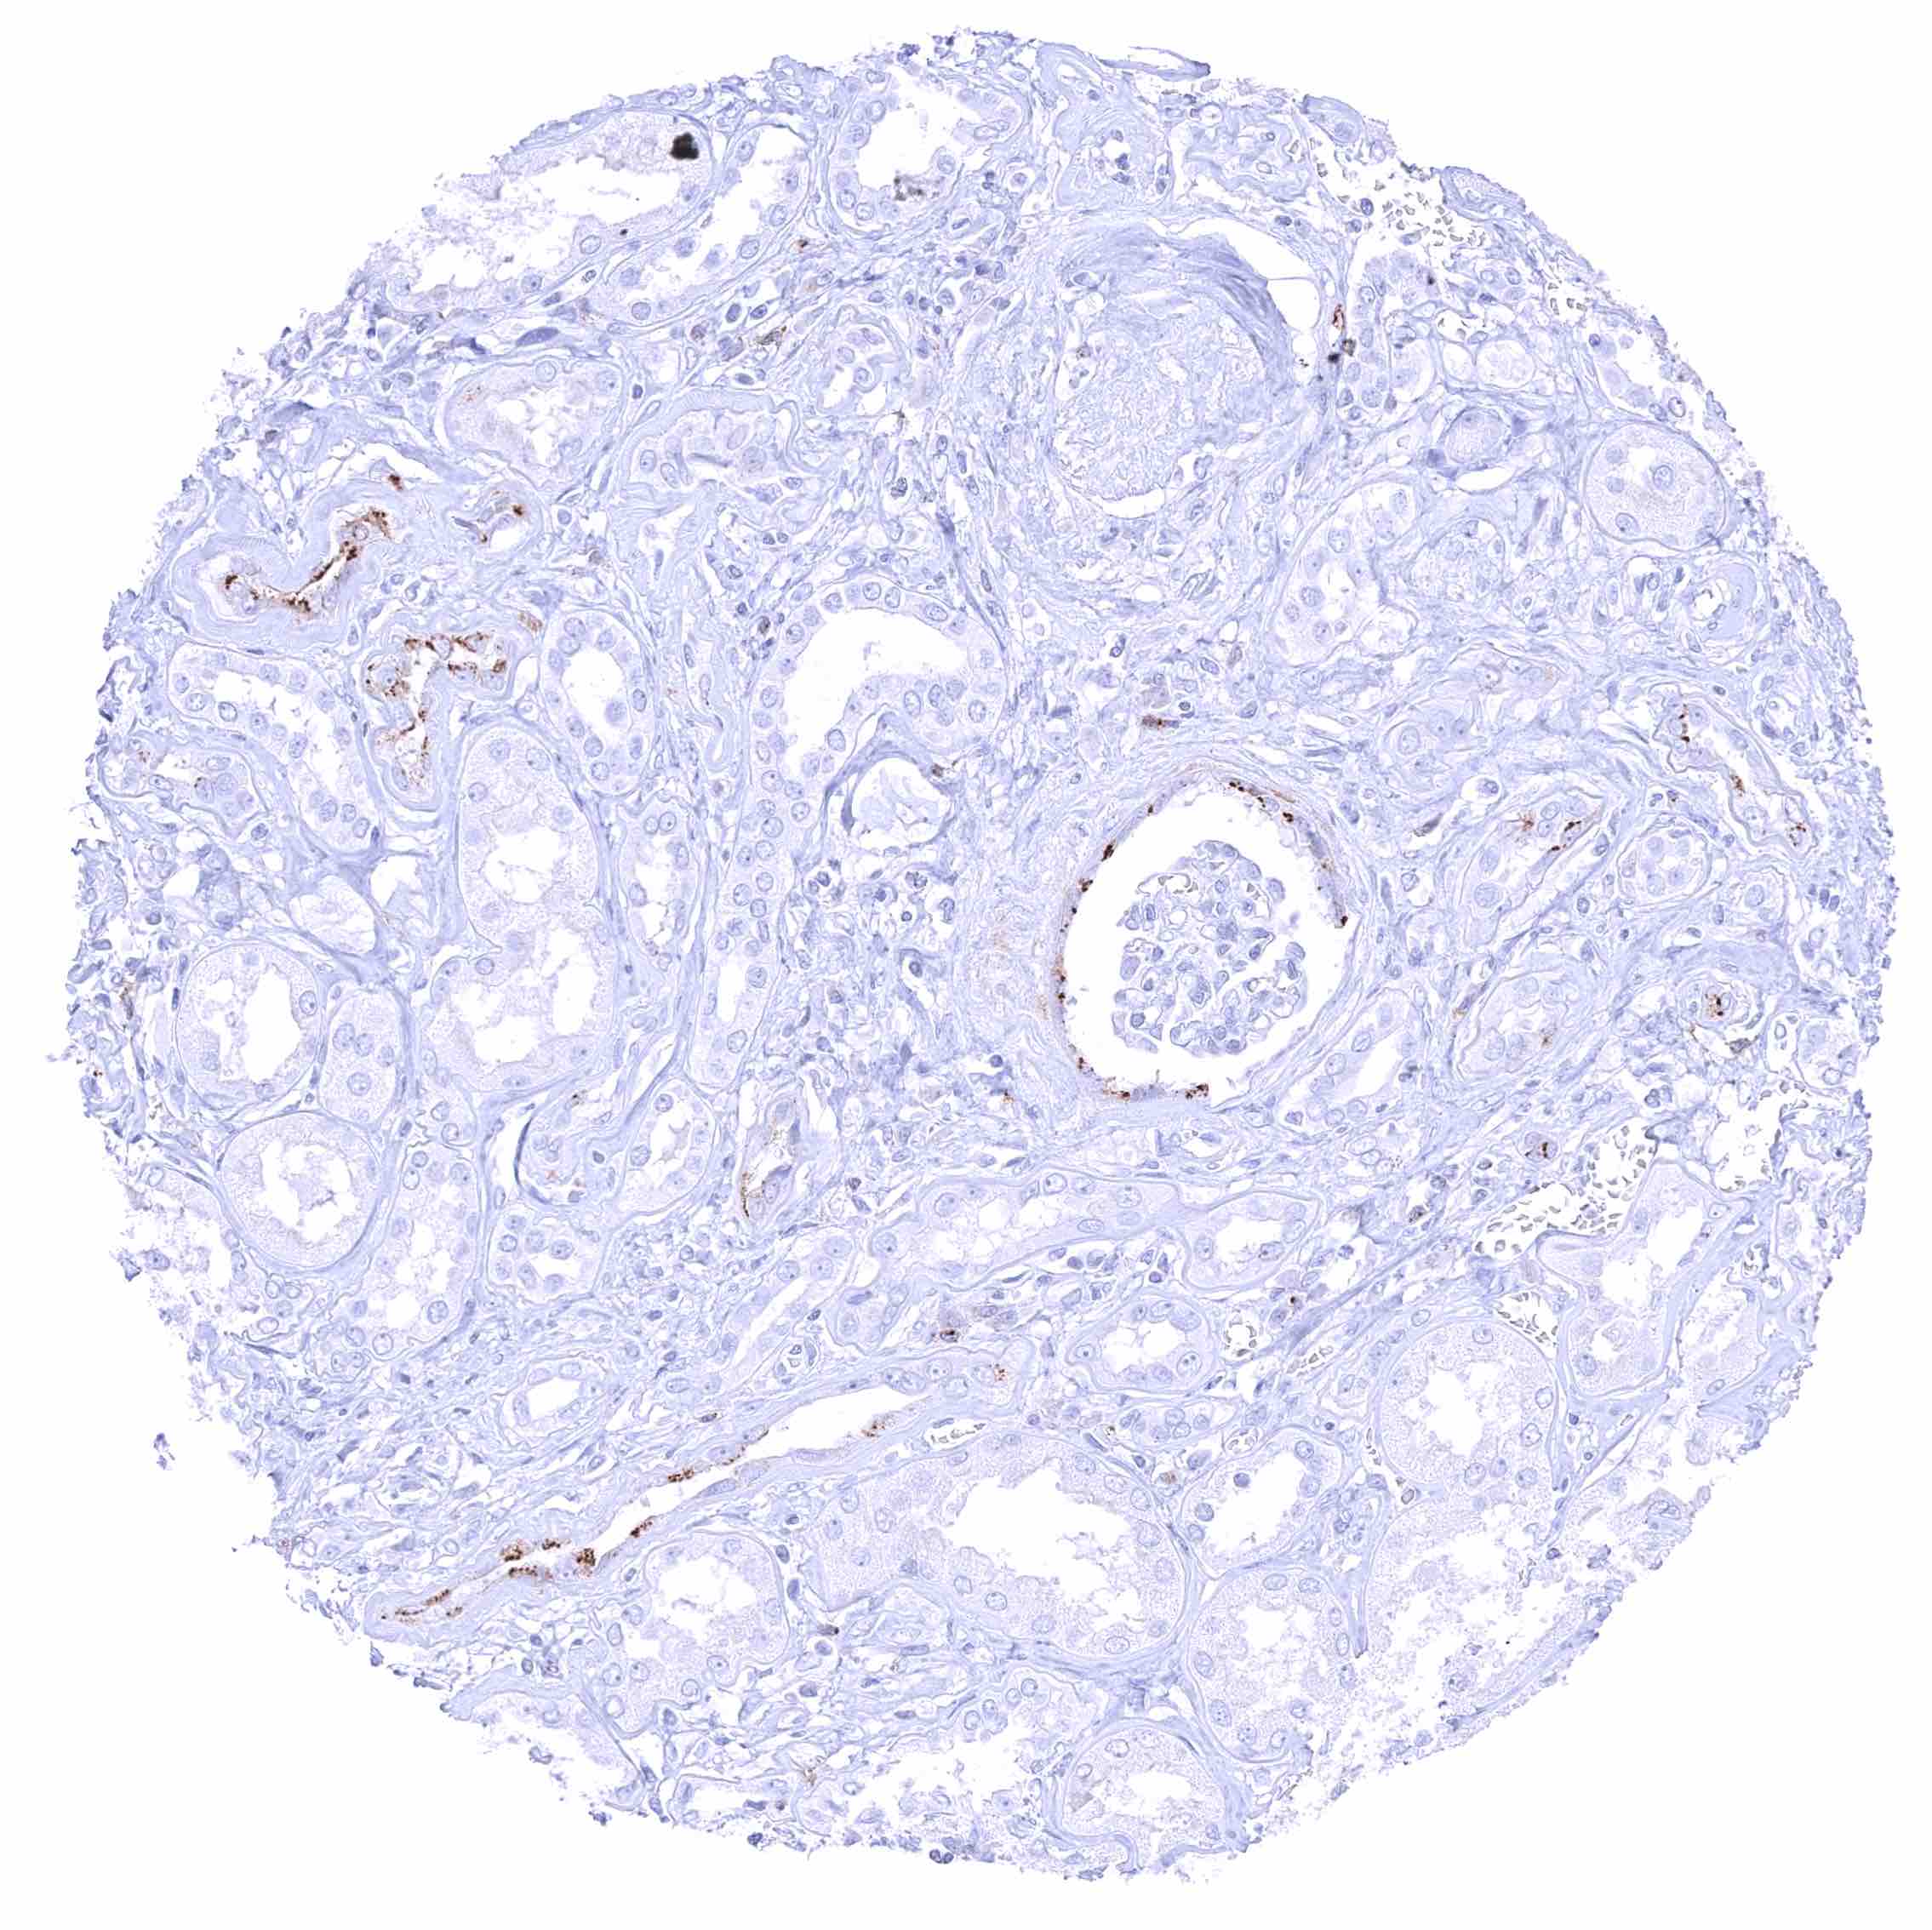

Tonsil – Membranous CD70 staining of variable intensity in subsets of cells (mostly lymphocytes). Most CD70 positive cells are interfollicular.